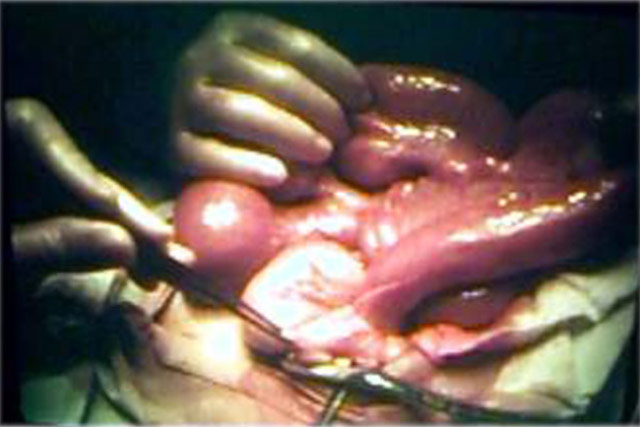

Invaginação Intestinal

com Necrose

Laparotomia mostrando a invaginação ileocecocólica.